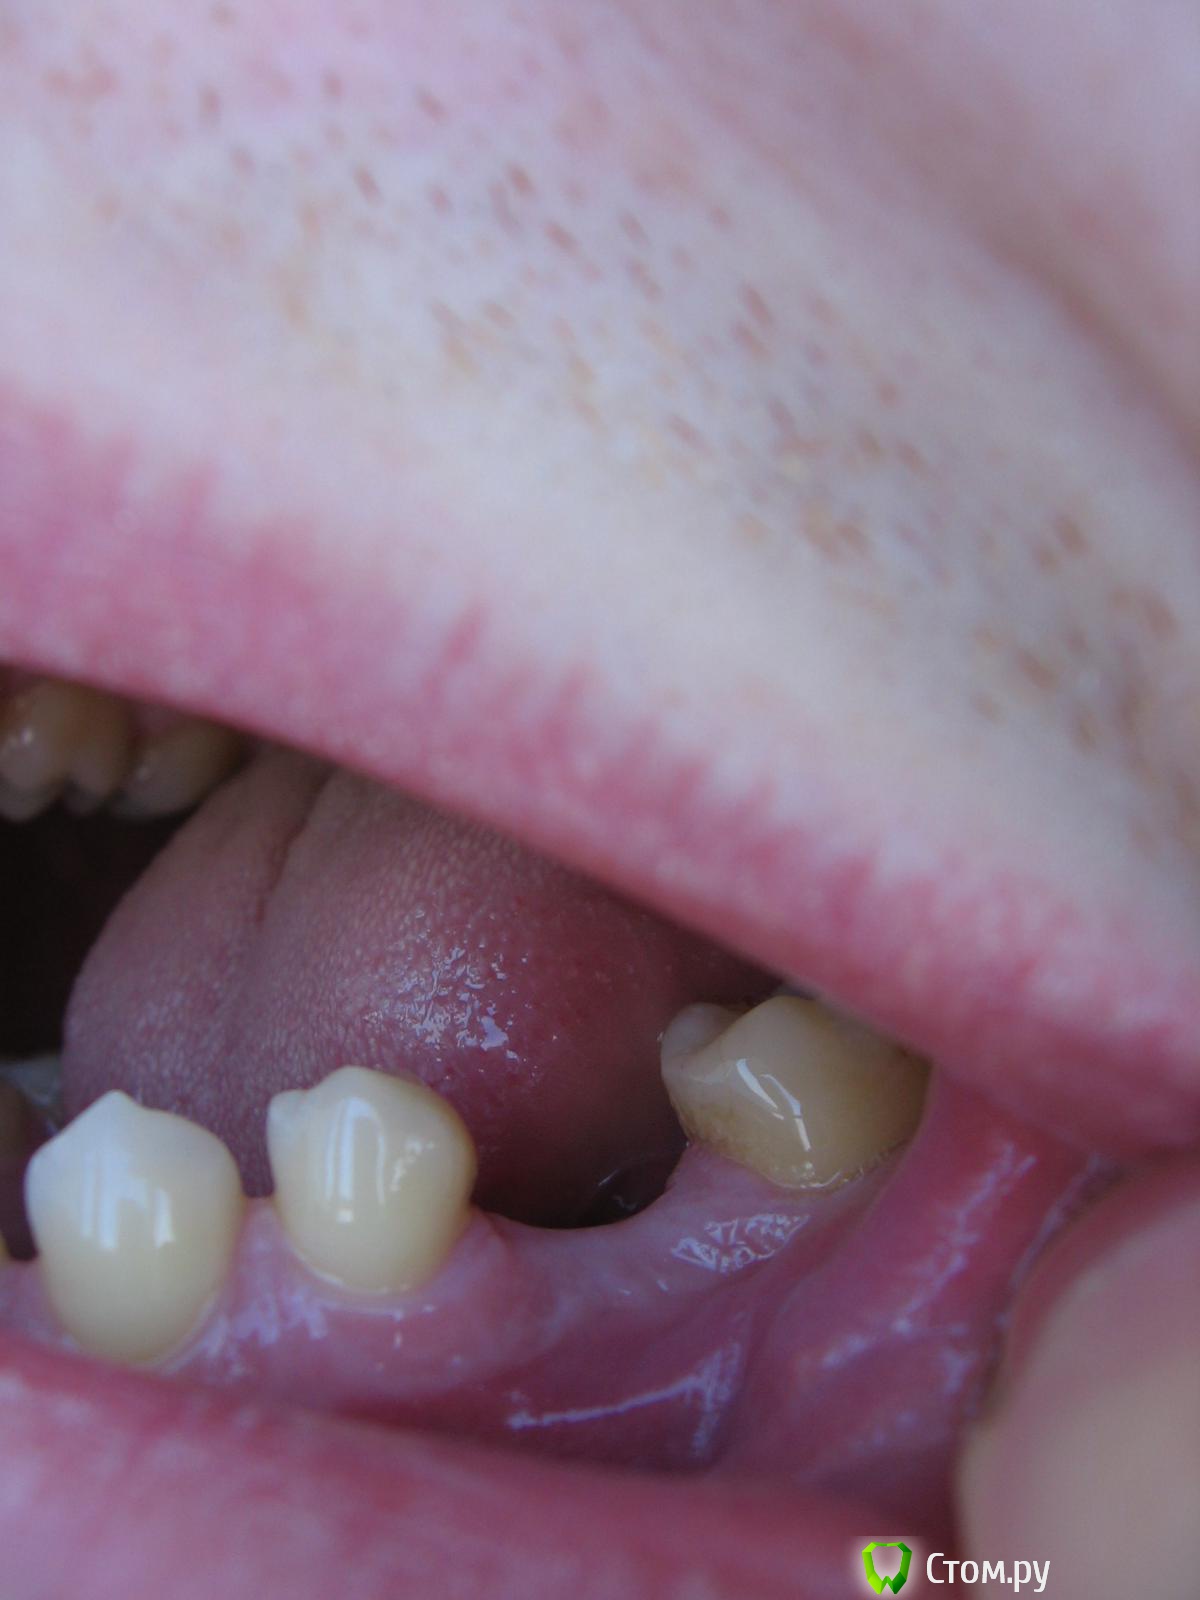

Bier Опубликовано 7 февраля, 2014 Поделиться Опубликовано 7 февраля, 2014 Спасибо. Раз здесь предпочитают винтовые импланты, спрошу следующее: Влияет ли костная пластика в моем случае на прогноз установленного винтового импланта? Т.е. она нужна только по эстетическим соображениям (поднять десну с внешней стороны) или же по гигиеническим тоже? Костная пластика остеопластическим материалом на мембране - это рутинная манипуляция, не несущая существенных рисков для пациента? Т.е. я могу довериться хирургу, который ее предложил? 1. я не знаю Вашей ситуации. Одного панорамного снимка недостаточно, нужны либо внутриротовые фотки либо срезы КТ.2. Существенных рисков нет, максимум неприятного- все развалится и придется начинать сначала. Ссылка на комментарий

bobrdobr Опубликовано 7 февраля, 2014 Автор Поделиться Опубликовано 7 февраля, 2014 Про пластику понял. Фото - без проблем. Изловчился сделать такие. КТ могу сделать, если она необходима. Ссылка на комментарий

IvanK Опубликовано 7 февраля, 2014 Поделиться Опубликовано 7 февраля, 2014 фото не информативны. как минимум, увеличить объем десны придется. Ссылка на комментарий